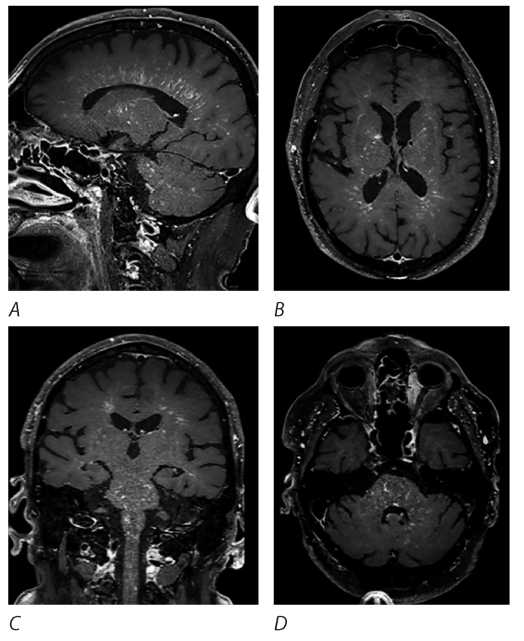

Спустя 2 мес после выписки (октябрь 2021 г.), на фоне снижения суточной дозы преднизолона до 20 мг/сут — рецидив заболевания в виде нарастания выраженной общей слабости, сонливости, когнитивных нарушений, шаткости при ходьбе. При МРТ головного и спинного мозга (октябрь 2021 г.): отрицательная динамика в виде увеличения количества Т2-гиперинтенсивных очагов в глубоких и перивентрикулярных отделах белого вещества головного мозга, а также более выраженное и интенсивное накопление КВ в белом веществе полушарий большого мозга, в стволе (преимущественно мост и средние мозжечковые ножки), интрамедуллярными очагами (рис. 1). Проведена пульс-терапия метилпреднизолоном в суммарной дозировке 5 г, на фоне чего симптоматика значительно регрессировала. Назначена пероральная терапия преднизолоном в дозе 80 мг/сут с последующим постепенным снижением.

Рис. 1. МРТ головного и спинного мозга пациента М. (октябрь 2021 г.).

A — Т2/T2-FLAIR ВИ: множественные очаги повышения интенсивности МР-сигнала в белом веществе полушарий головного мозга (имеющие протяжённый характер и периваскулярный паттерн локализации), в мосту, продолговатом мозге, средних ножках мозжечка; B — Т1+С: линейное радиальное периваскулярное накопление КВ в белом веществе полушарий, в стволе, ножках мозга, мозжечке; C — Т2/T2-STIR ВИ: множественные очаги с нечёткими контурами повышения интенсивности МР-сигнала в спинном мозге на всём протяжении; D — Т1+С: точечное неоднородное накопление КВ в веществе спинного мозга.

Fig. 1. Patient M.’s brain and spinal MRI (October 2021).

A — Т2/T2-FLAIR: multiple hyperintense white matter lesions in the cerebral hemispheres (elongated and perivascular), the pons, the medulla oblongata, and the middle cerebellar peduncles; B — Т1+С: linear radial perivascular contrast enhancement in the white matter of the cerebral hemispheres, the brainstem, the cerebral peduncles, and the cerebellum; C — Т2/T2-STIR: multiple ill-defined hyperintense lesions along the entire length of the spinal cord; D — Т1+С: focal heterogeneous contrast enhancement in the spinal cord.